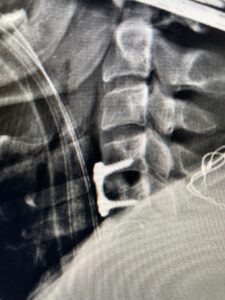

Fig. 3 Intraoperative lateral cervical X-Ray demonstrating C4-5 ACDF